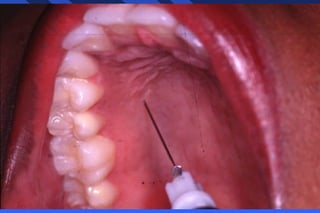

TechniqueTechnique

Apply topical, pressureApply topical, pressure

Insert into gingiva in center of areaInsert into gingiva in center of area

- 5-10 mm from gingival margin- 5-10 mm from gingival margin

Aspirate (positive results are rare)Aspirate (positive results are rare)

Inject 0.2-.3 ml, slowlyInject 0.2-.3 ml, slowly